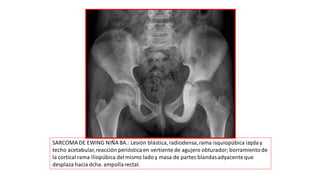

SARCOMA DE EWING NIÑA 8A.: Lesión blástica,radiodensa,rama isquiopúbica izqday

techo acetabular,reacción perióstica en vertiente de agujero obturador; borramientode

la cortical rama iliopúbica delmismo ladoy masa de partes blandasadyacenteque

desplaza hacia dcha. ampollarectal.